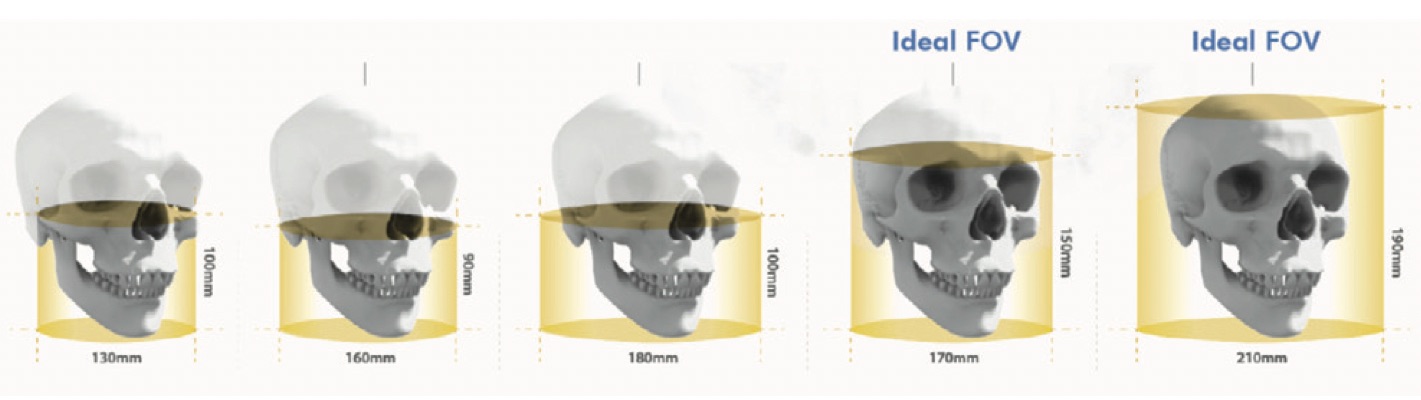

Además, en un equipo CBCT el haz de rayos X tiene forma cónica y obtiene un volumen de datos cilíndrico o esférico que se conoce como FOV (field of view). El tamaño del FOV difiere en los distintos escáneres, siendo algunos capaces de capturar el esqueleto maxilofacial completo. También algunos equipos CBCT pueden ajustar la altura del FOV cilíndrico para capturar una sola zona, lo que reduce la dosis de radiación al paciente.

Esquema que muestra los distintos tamaños de FOV en CBCT.

De acuerdo al FOV podemos clasificar los equipos CBCT en sistemas de gran FOV (15-30,5 cm.) y sistemas de FOV limitado (4 a 8 cm.). Esto es importante porque:

A mayor FOV:

- Imagen más extensa del área anatómica

- Mayor exposición a la radiación

- Menor resolución de las imágenes

A menor FOV:

- Imagen de una pequeña parte del área anatómica

- Menor exposición a la radiación

- Mayor resolución de las imágenes

Para las aplicaciones de la odontología en las cuales no se requiera de un máximo detalle de las estructuras, pero si de una representación más significativa de la cara, como la ortodoncia o la planificación de implantes, se podría sacar mayor provecho de un escáner CBCT de gran o moderado FOV. Pero, por ejemplo, cuando se requiere realizar un diagnóstico de alteraciones dentales, se necesita una imagen con mayor precisión de una pequeña parte y en este caso sería más apropiado el uso de un sistema CBCT de FOV limitado. Veamos más en detalle las distintas aplicaciones de un escáner CBCT en la clínica dental: